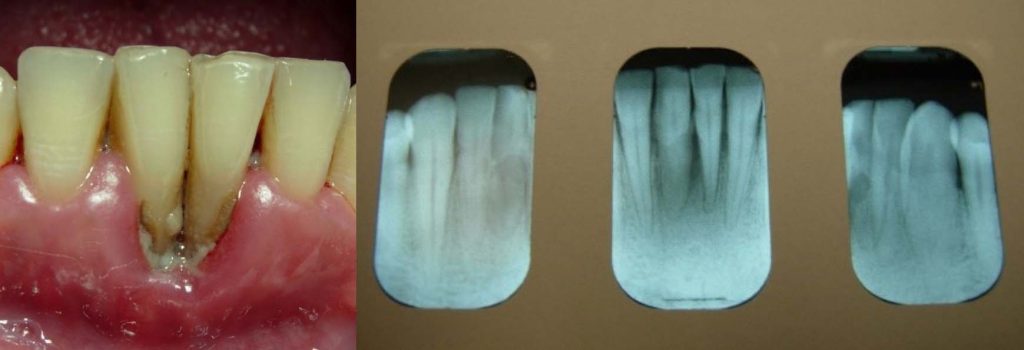

About half of the U.S. population >30 years of age is affected by chronic periodontal disease, and the prevalence of periodontal disease increases with age Eke, et al. 2015. No data currently exist to indicate the extent to which HIV infection may accelerate the destruction of periodontal tissues in the population with HIV. However, the occurrence of rapid attachment loss may indicate severe immunosuppression Ryder, et al. 2012; Mealey 1996. Pre-existing periodontal disease can be diagnosed by clinical characteristics and radiographic examination for bone loss as recommended by the American Academy of Periodontology American Academy of Periodontology 2000; Armitage 1999. The clinical characteristics for chronic periodontitis include the presence of periodontal pockets, clinical attachment loss, and bleeding on probing. Radiographic analysis can reveal the presence of periodontal bone loss with horizontal or vertical bony defects. Increased mobility of teeth may also be observed in association with clinical attachment loss and bone loss.

Appendix: Photo- and Radiographs of Periodontal Disease Associated With HIV

Photographs courtesy of Dr. Gwen Cohen Brown and the Dental Hygiene Department of New York City College of Technology

Figure 5: Patient with localized bone loss